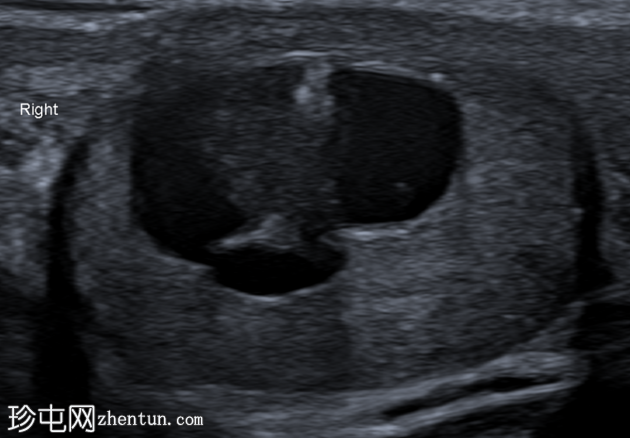

超声检查

右侧睾丸内可见一异质性肿块,大小约10 x 14 x 15 mm,包含实性和囊性成分。肿块内可见多发小钙化灶。彩色多普勒超声检查显示肿块内血流信号较少。